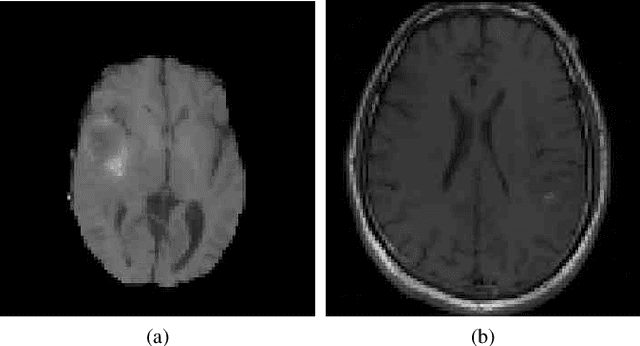

Abstract:The analysis of Magnetic Resonance Imaging (MRI) sequences enables clinical professionals to monitor the progression of a brain tumor. As the interest for automatizing brain volume MRI analysis increases, it becomes convenient to have each sequence well identified. However, the unstandardized naming of MRI sequences makes their identification difficult for automated systems, as well as makes it difficult for researches to generate or use datasets for machine learning research. In the face of that, we propose a system for identifying types of brain MRI sequences based on deep learning. By training a Convolutional Neural Network (CNN) based on 18-layer ResNet architecture, our system can classify a volumetric brain MRI as a FLAIR, T1, T1c or T2 sequence, or whether it does not belong to any of these classes. The network was evaluated on publicly available datasets comprising both, pre-processed (BraTS dataset) and non-pre-processed (TCGA-GBM dataset), image types with diverse acquisition protocols, requiring only a few slices of the volume for training. Our system can classify among sequence types with an accuracy of 96.81%.